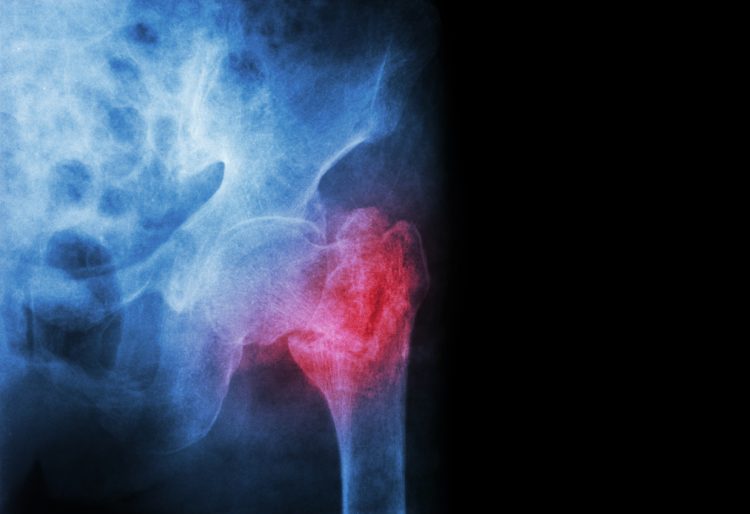

Kliniken, die Patientinnen und Patienten mit Oberschenkelhalsbrüchen (hüftgelenknaher Femurfraktur) behandeln, müssen die seit dem Jahr 2021 geltenden Qualitätsvorgaben weiterhin noch nicht vollständig erfüllen.

Die neuen Strukturqualitätsvorgaben des G-BA sollen sicherstellen, dass Oberschenkelhalsbrüche in Deutschland flächendeckend innerhalb von 24 Stunden operiert werden und alle wichtigen Abläufe dabei zuverlässig eingehalten werden.